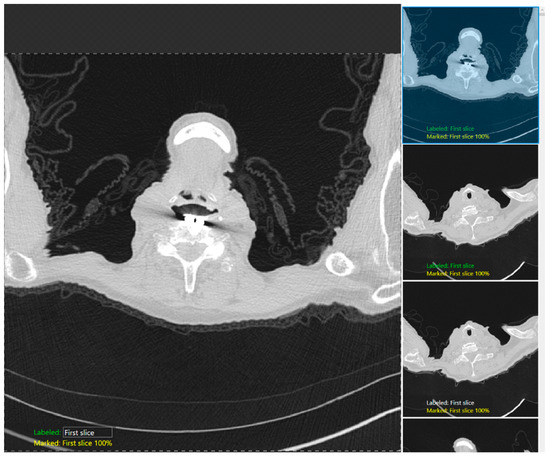

Low-Dose CT Quality Assurance at Scale: Automated Detection of Overscanning, Underscanning, and Image Noise

Automated quality assurance is essential for low-dose computed tomography (LDCT) lung screening, yet manual checks strain clinical workflows. We present a fully automated artificial intelligence tool that quantifies scan coverage and image noise in LDCT without user input. Lungs and the aorta are segmented to measure cranial/caudal over- and underscanning, and noise is computed as the standard deviation of Hounsfield units (HUs) within descending aortic blood, normalized to a 1 mm3 voxel. Performance was verified in a reader study of 98 LDCT scans from the National Lung Screening Trial (NLST), and then applied to 38,834 NLST scans reconstructed with a standard kernel. In the reader study, lung masks were rated ≥“Nearly Perfect” in 90.8% and aorta-blood masks in 96.9% of cases. Across 38,834 scans, mean overscanning distances were 31.21 mm caudally and 14.54 mm cranially; underscanning occurred in 4.36% (caudal) and 0.89% (cranial). The tool enables objective, large-scale monitoring of LDCT quality—reducing routine manual workload through exception-based human oversight, flagging protocol deviations, and supporting cross-center benchmarking—and may facilitate dose optimization by reducing systematic over- and underscanning. Full article

Figure 1